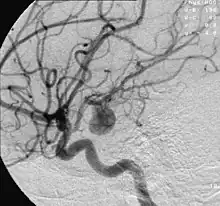

Et aneurisme (fra græsk ἀνεύρυσμα, udvidelse) er en unormal lokal udvidelse af en pulsåre (arterie). Aneurismer forekommer hyppigst i aorta (hovedpulsåren) og Willis' arterielle cirkel (pulsårerne under hjernen). Aneurismer skyldes en svækkelse af karvæggen, og dette kan skyldes både arvelige faktorer og erhvervet sygdom.

Aneurismer giver ikke nødvendigvis anledning til problemer og opdages ofte slet ikke. Diagnosen kan stilles ved undersøgelse af blodkarrene med ultralyd eller scanning. Hvis udposningen er meget stor, er der risiko for at den brister (ruptur), hvilket udløser pludselig blødning med høj risiko for død.